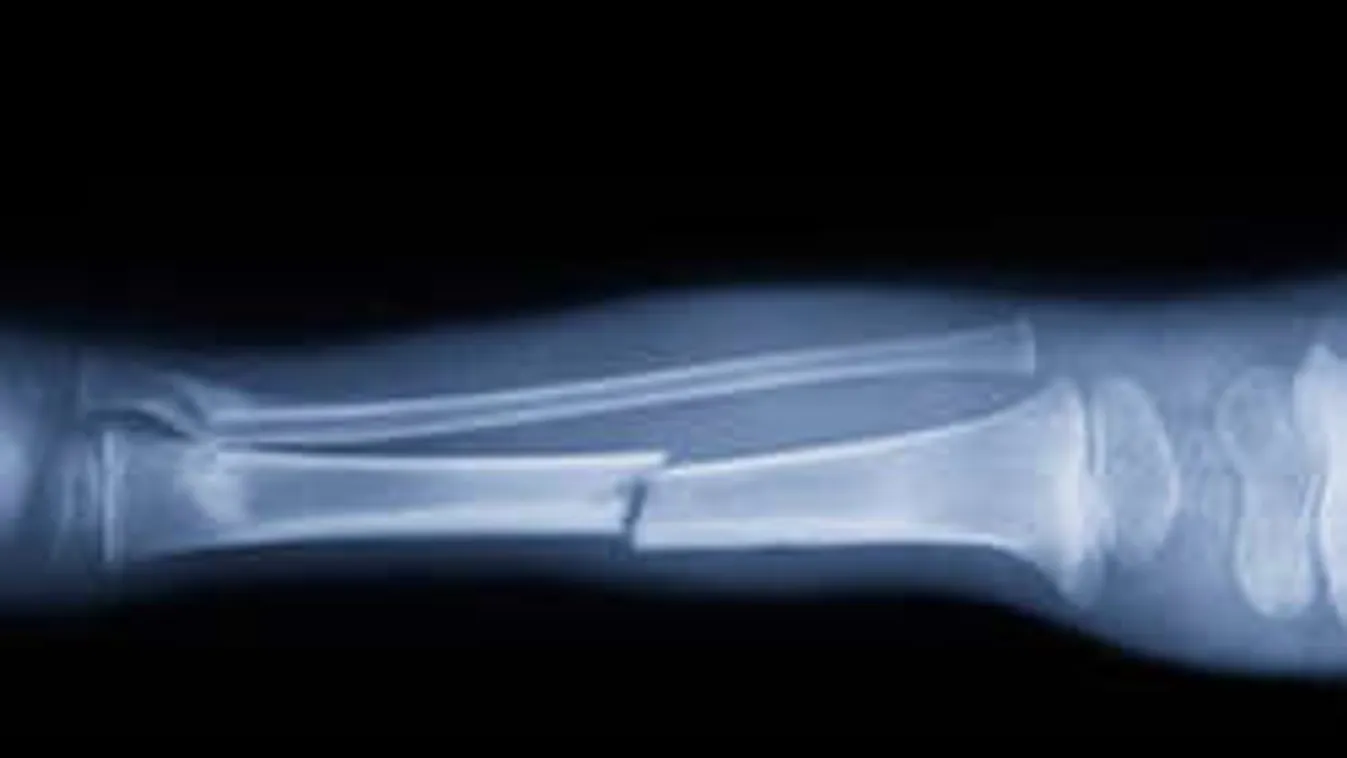

Kapaszkodj meg: híg cementet fecskendeznek a törött és szétcsúszott csont közötti hézagba. A csontbarát cementtel napok alatt összeforrhat a sérült csont!

Idegőrlő, amikor egy lábgipsz miatt hetekig feküdni kell, de az se jobb, ha a kezedet nem tudod használni egy törött csont miatt. Sajnos a sérült csontoknak viszonylag hosszú időre, akár több hétre van szükségük a regenerációhoz. Ezen segíthet az úgynevezett kalcium-foszfát (CMC), a csontbarát cement. Francia tudósok felfedezték, ha ezt az anyagot oldott állapotban a törött csontba fecskendezik, akkor az akár napok alatt összeforrhat, pont úgy, mintha hetekig várnánk rá.